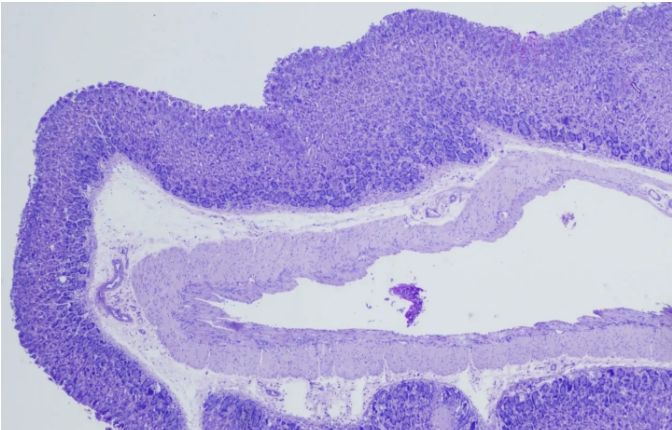

PAS染色實驗過程中常見問題解答由普拉特澤生物為大家總結分享。PAS染色作為一種在組織學中廣泛應用的染色技術,雖然具有高度的特異性和敏感性,但在實際操作過程中,也常會遇到一些問題和挑戰。本文是關于PAS染色實驗的最后一篇介紹,前面我們學習了PAS染色實驗材料有哪些?、PAS染色和mpo染色區別是什么?、PAS染色實驗注意事項以及PAS染色臨床應用,可以點擊標題直接傳送回去學習的哦。普拉特澤生物組織染色檢測平臺承接酵母雙雜實驗外包上百例,早就為大家把實驗過程中要踩的雷、吃的虧幫大家吃完了,現在我們就來看看,PAS染色中常見問題的解答:

綜上所述,PAS染色雖然是一種常用的組織學染色方法,但在實際操作中常常會遇到一些問題。通過掌握常見問題及其解決方法,我們可以更好地應用這項技術,提高染色效果和觀察結果的準確性。同時,不斷學習和實踐也是提高PAS染色技術水平的重要途徑。